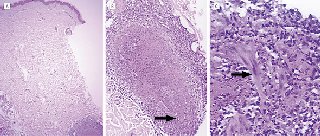

El estudio histológico de la biopsia obtenida de la mucosa nasal

mostró la presencia de una vasculitis necrotizante con presencia

de numerosos histiocitos, compatible con enfermedad de Wegener.

A pesar del tratamiento antibiotico instaurado la artritis y la fiebre persistieron y aparecieron nuvas lesiones cutáneas en manos y cadera. Se practico una biopsia cutánea de una de las lesiones que mostro depositos de material amorfo eosinofílico en dermis con presencia de neutrofilos y rodeados de histiocitos epitelioides y la presencia de remanentes de musculo liso consistentes con una vasculitis granulomatosa y neutrofilica trombotica afectando las arterias musculares (Fig 2). También se observouna vasculitis de pequeño vasode predominio neutrofilico con presencia de infiltrado inflamatorio mixto compuesto por linfocitos, plasmocitos y histiocitos.